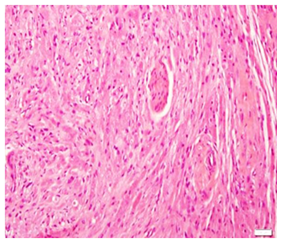

An excision biopsy specimen from a mass at elbow of 26 years old female patient was received for histopathological examination. The clinical impression was of ‘benign soft tissue tumor’. The specimen was received in 10% formalin in one container. On gross examination, it was a 1.5 x 1 x 0.5 cm well-circumscribed, grey-tan mass, without skin component. The cut surface was solid homogenous and no necrotic or hemorrhagic areas were found on it. The microscopic examination revealed a circumscribed encapsulated lesion composed of round to polygonal to spindle shaped cells with eosinophilic granular cytoplasm and centrally placed small nuclei (Figure 1 & Figure 2). Cells were arranged in intersecting bundles and mixed with fibrous connective tissue (Figure 3). The Intralesional peripheral nerve bundles surrounded by the lesional cells were seen (Figure 4). No significant mitoses or cells with cross striation, significant inflammatory infiltrate or necrosis were seen. IHC showed positive results for S100 (Figure 5) and neuron-specific Enolase (NSE) (Figure 6). Smooth muscle actin (SMA) (Figure 7) and Myogenin were negative. CEA was focally positive. Periodic acid-schiff (PAS) stain showed PAS positive intracytoplasmic granules (Figure 8). The lesion was completely excised with <1mm safety margin. Focal entrapment of the adjacent fatty tissue was observed. Based on the above mentioned findings, diagnosis of granular cell tumor (GCT) was made.

Figure 4 The Intralesional peripheral nerve bundles surrounded by the lesional cells.